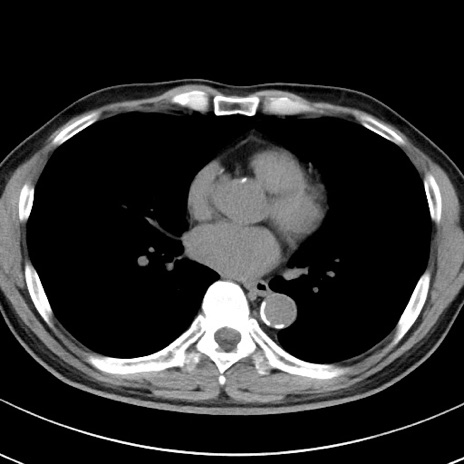

【腹部TIPS】症例29 参考症例 CT(横断像)

症例

70歳代男性